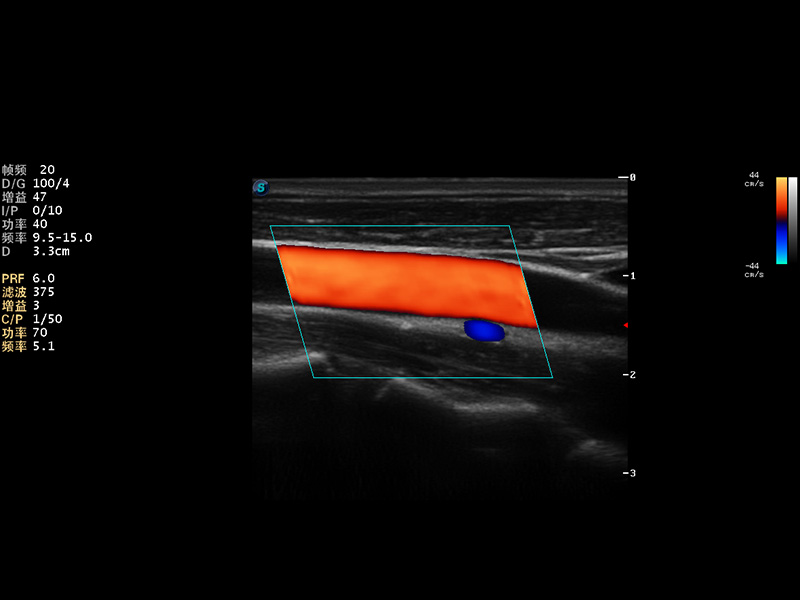

S9便携式彩色多普勒超声诊断仪是球速体育入口研发的高端便携彩超设备,外观设计新颖、产品性能卓越。S9在便携超声领域采用了突破传统的触摸屏交互设计,并以先进的软件硬件技术和设计理念,为您带来清晰的图像质量、稳定的工作性能和便捷的操作体验。

成像技术

AutoC智能血流追踪